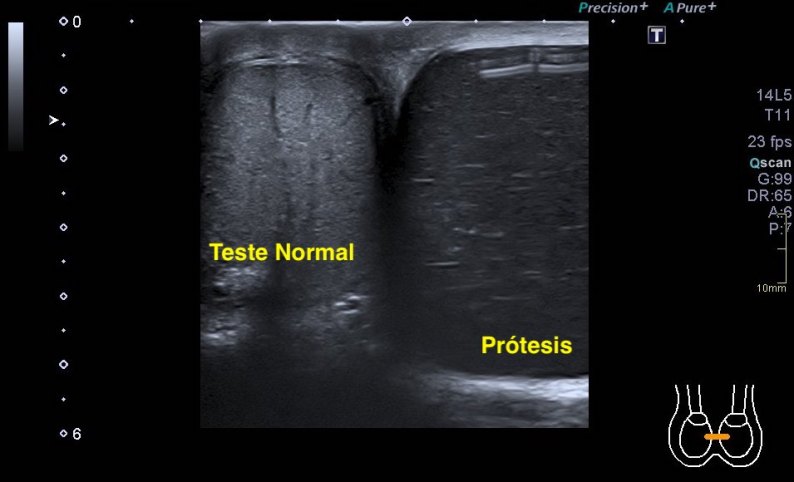

2.Tendón del subescapular

El tendón de subescapular es una estructura que no debe ir rodeada de líquido, por experiencia, cuando la presencia de líquido es evidente en esta localización, sabemos que la exploración depara alguna sorpresa más adelante en relación con rotura en algún tendón de más o menos envergadura.

Imagen superior, normalidad, imagen inferior, patología entre el deltoides y el subescapular. Te recomiendo encarecidamente la realización de la dinámica de este tendón, bajo la coracoides, donde desliza el subescapular, puede esconderse la bursa con líquido en la aducción que se revela visible en la abducción forzada, para el estudio de este tendón.